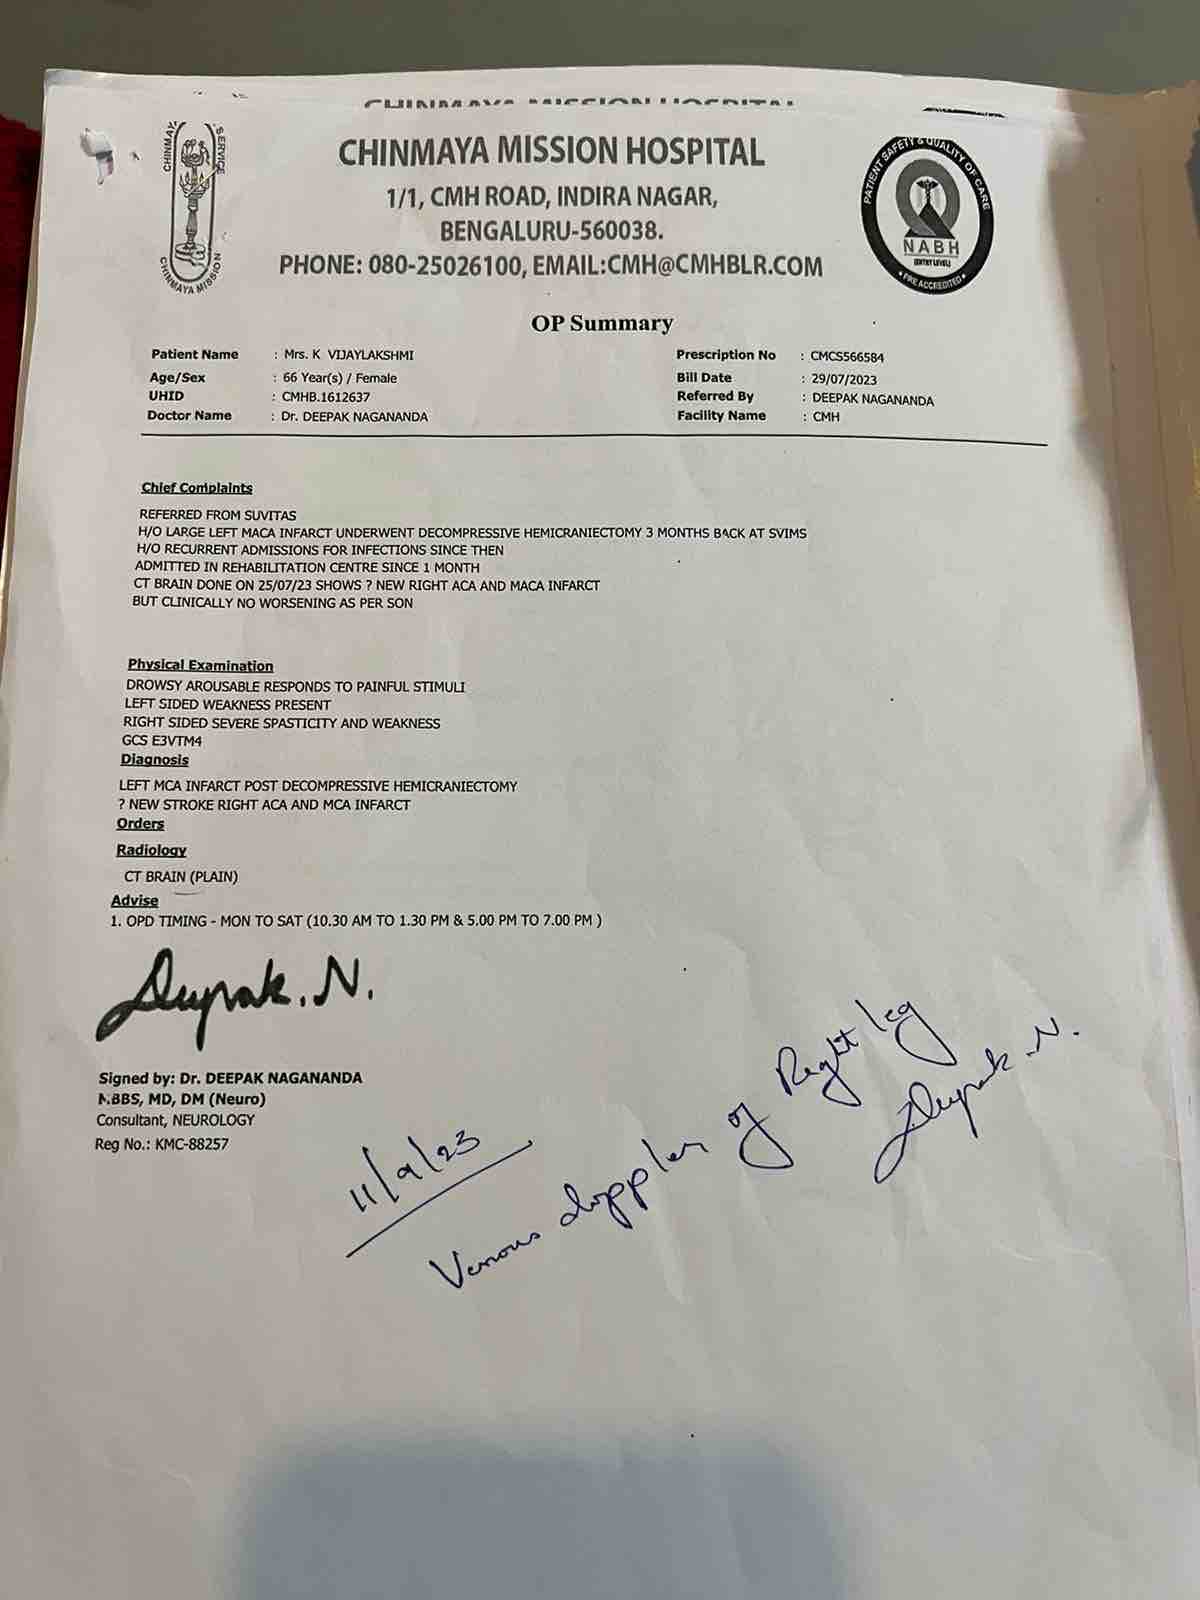

We are reaching out to you today with a heavy heart and a plea for help. Our beloved 66-year-old mother K VIJYA LAKSHMI, has been facing an incredibly challenging journey since 16th May when she had brain stroke & underwent emergency brain and abdomen surgery. Her recovery has been a rollercoaster of ups and downs.

During her hospitalization, she endured multiple complications, including respiratory distress, recurrent severe infections, and even seizure-like activity. Through it all, she has shown immense strength and determination. Still she require three more surgeries to stand on the path of recovery.